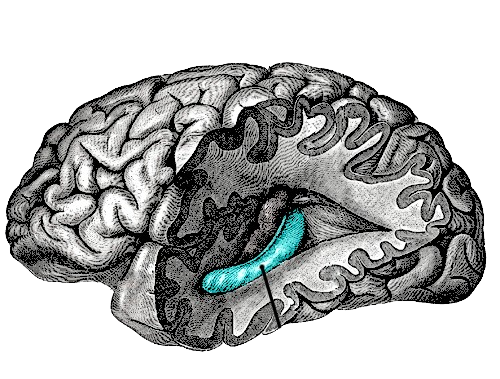

Engram research in rodents will point the way to methods for manipulating memories in people

In some cognitive disorders, it may be that you have too little forgetting, and instead you get too many active memories interfering with the target one you’re trying to recall ... The brain isn’t like a hard drive on a computer, it doesn’t get full.